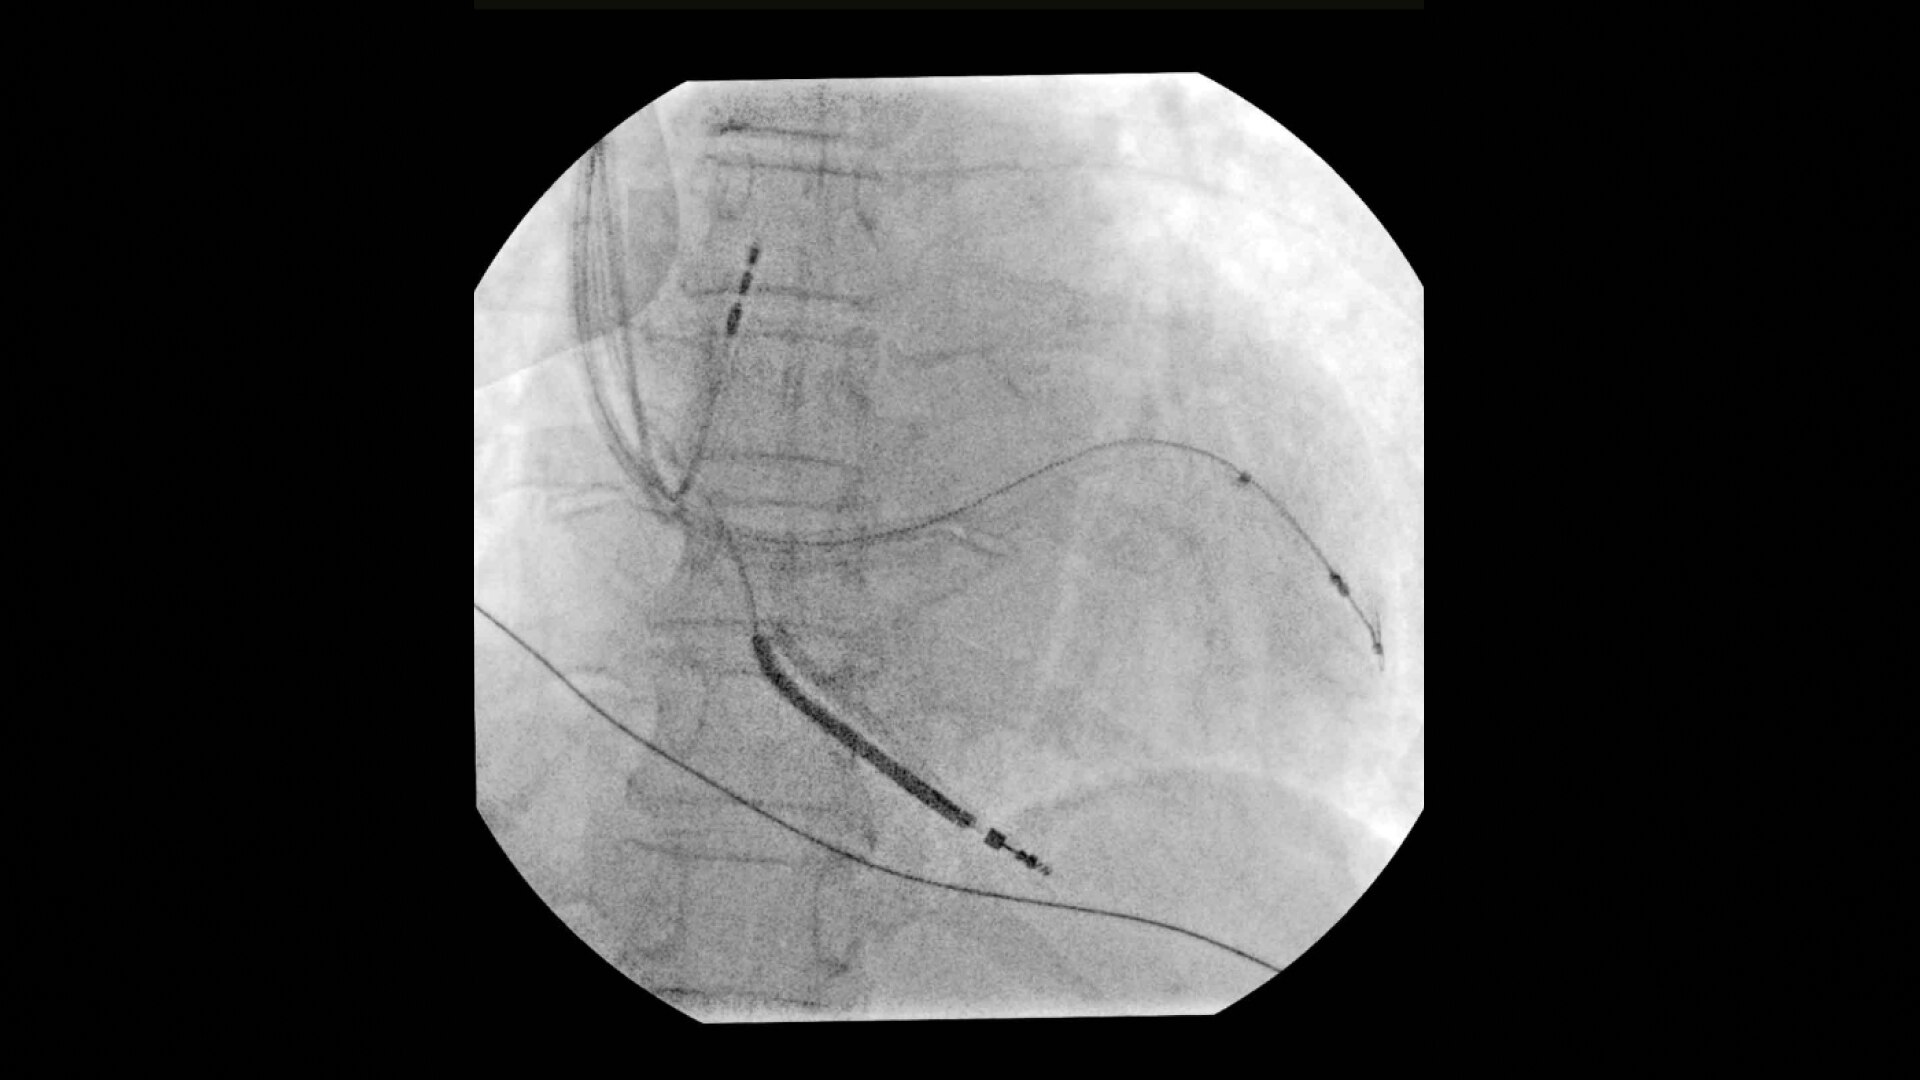

Achieve high-quality visualization necessary for complex cardiac procedures. OEC C-arms offer amazing image quality at low dose for efficient interventional imaging. Interventionalists and surgeons clearly see fine details of cardiac imaging, such as the border of the heart, leads, and small guidewires. Dynamic range management enables superb resolution, even with motion, during cardiac procedures.

See 0.014” guidewires in thoracic region or wire leads when placing biventricular pacemakers with the OEC Elite CFD flat detector, image processing, and 4K display.

Cardiac imaging you need

Complex cardiac procedures require powerful imaging systems.

OEC premium C-arms perform a variety of procedures such as:

• Cardiac resynchronization therapy device implant

• Multisite pacemaker implant